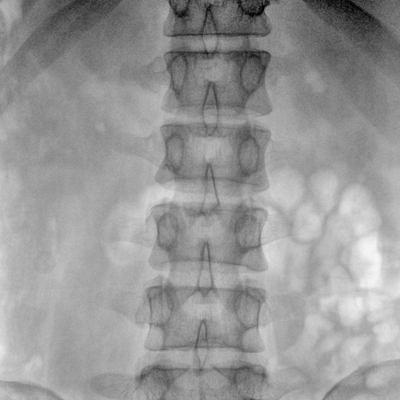

大尺寸動態(tài)平板探測器,高DQE、低噪聲、圖像清晰。采用多分辨率圖像增強處理技術(shù),不同部位不同圖像處理算法,滿足客戶多樣化的需求。

采用智能變頻脈沖透視技術(shù),優(yōu)化圖像質(zhì)量的同時降低輻射劑量,呵護醫(yī)患健康